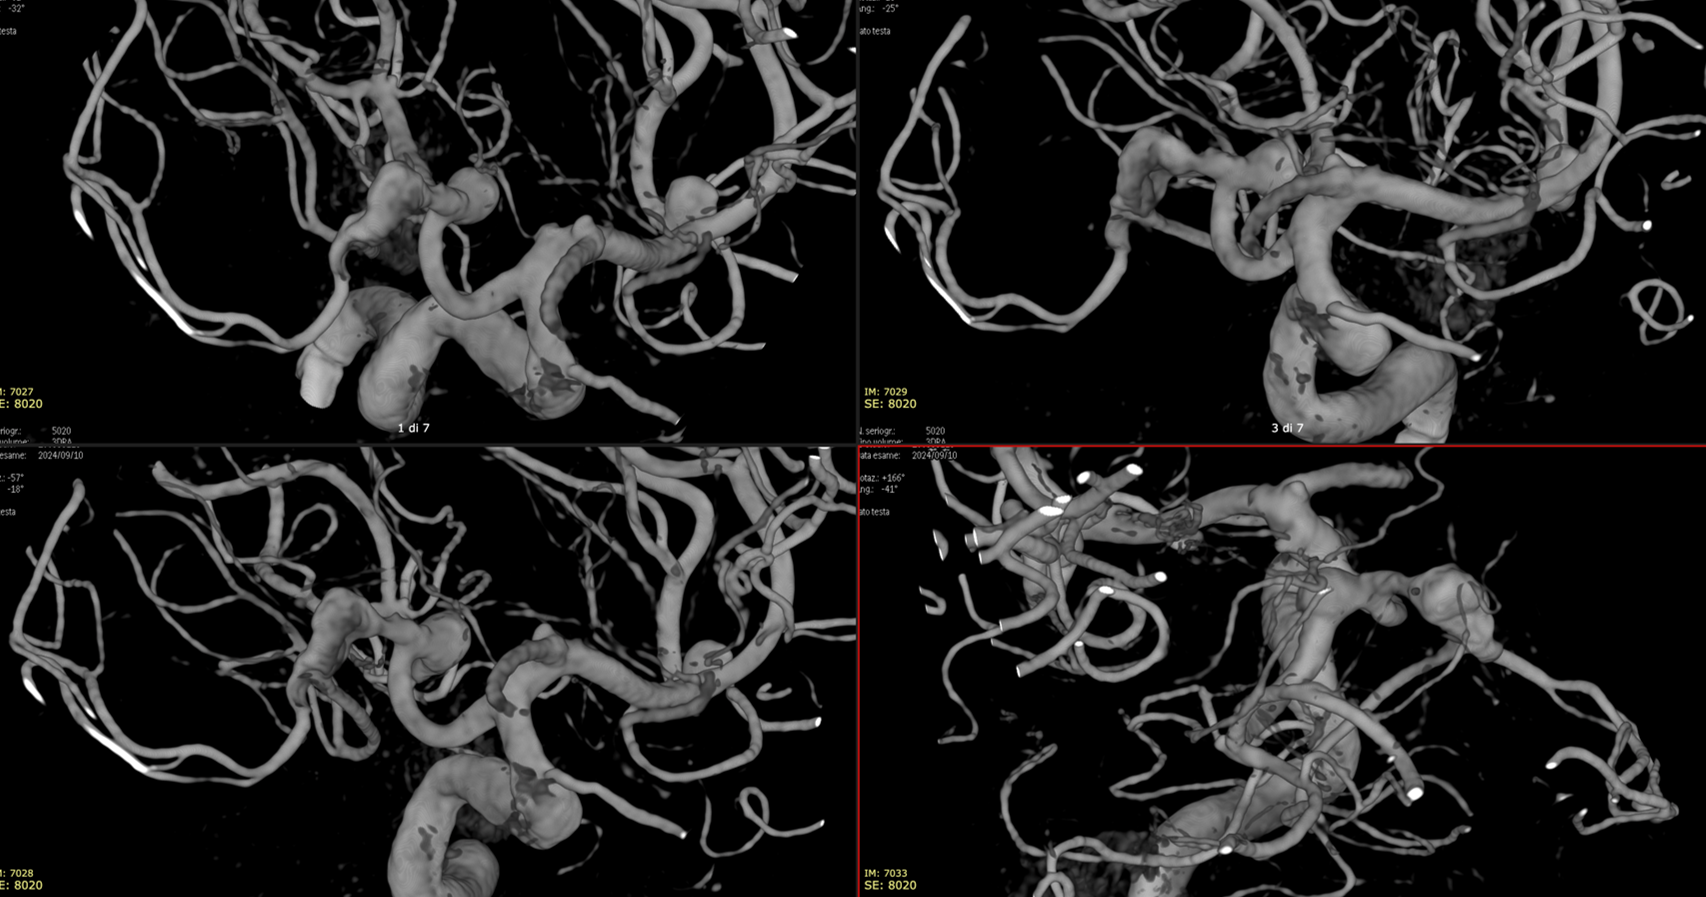

A symptomatic unruptured MCA bifurcation aneurysm in a young woman

This video was made with Horos from the original 3D dataset (3D 5 seconds 15 cm FOV acquisition, manually injecting pure contrast – 250 mg/ml – with a 20 ml syringe).

Wide neck MCA trifurcation aneurysm.

Y stenting with Atlas and Lvis Evo, in emergency. The Atlas diameter was too large because of the temporary limited availability in our centre; we can clearly see the struts of the Atlas too open at the level of the aneurysm neck (arrow). Even the microcatheter for coiling is fully visible jailed by the Lvis Evo in M1

The injection of contrast medium (250 mg/ml, 50% dilution, manual injection, same reconstruction protocol as previous images) reduces the visibility of the struts — an important point to consider. Not everything is always the same contrast dilution, same injection rate, etc. etc. — you need to know how to vary every parameter to achieve desired results.